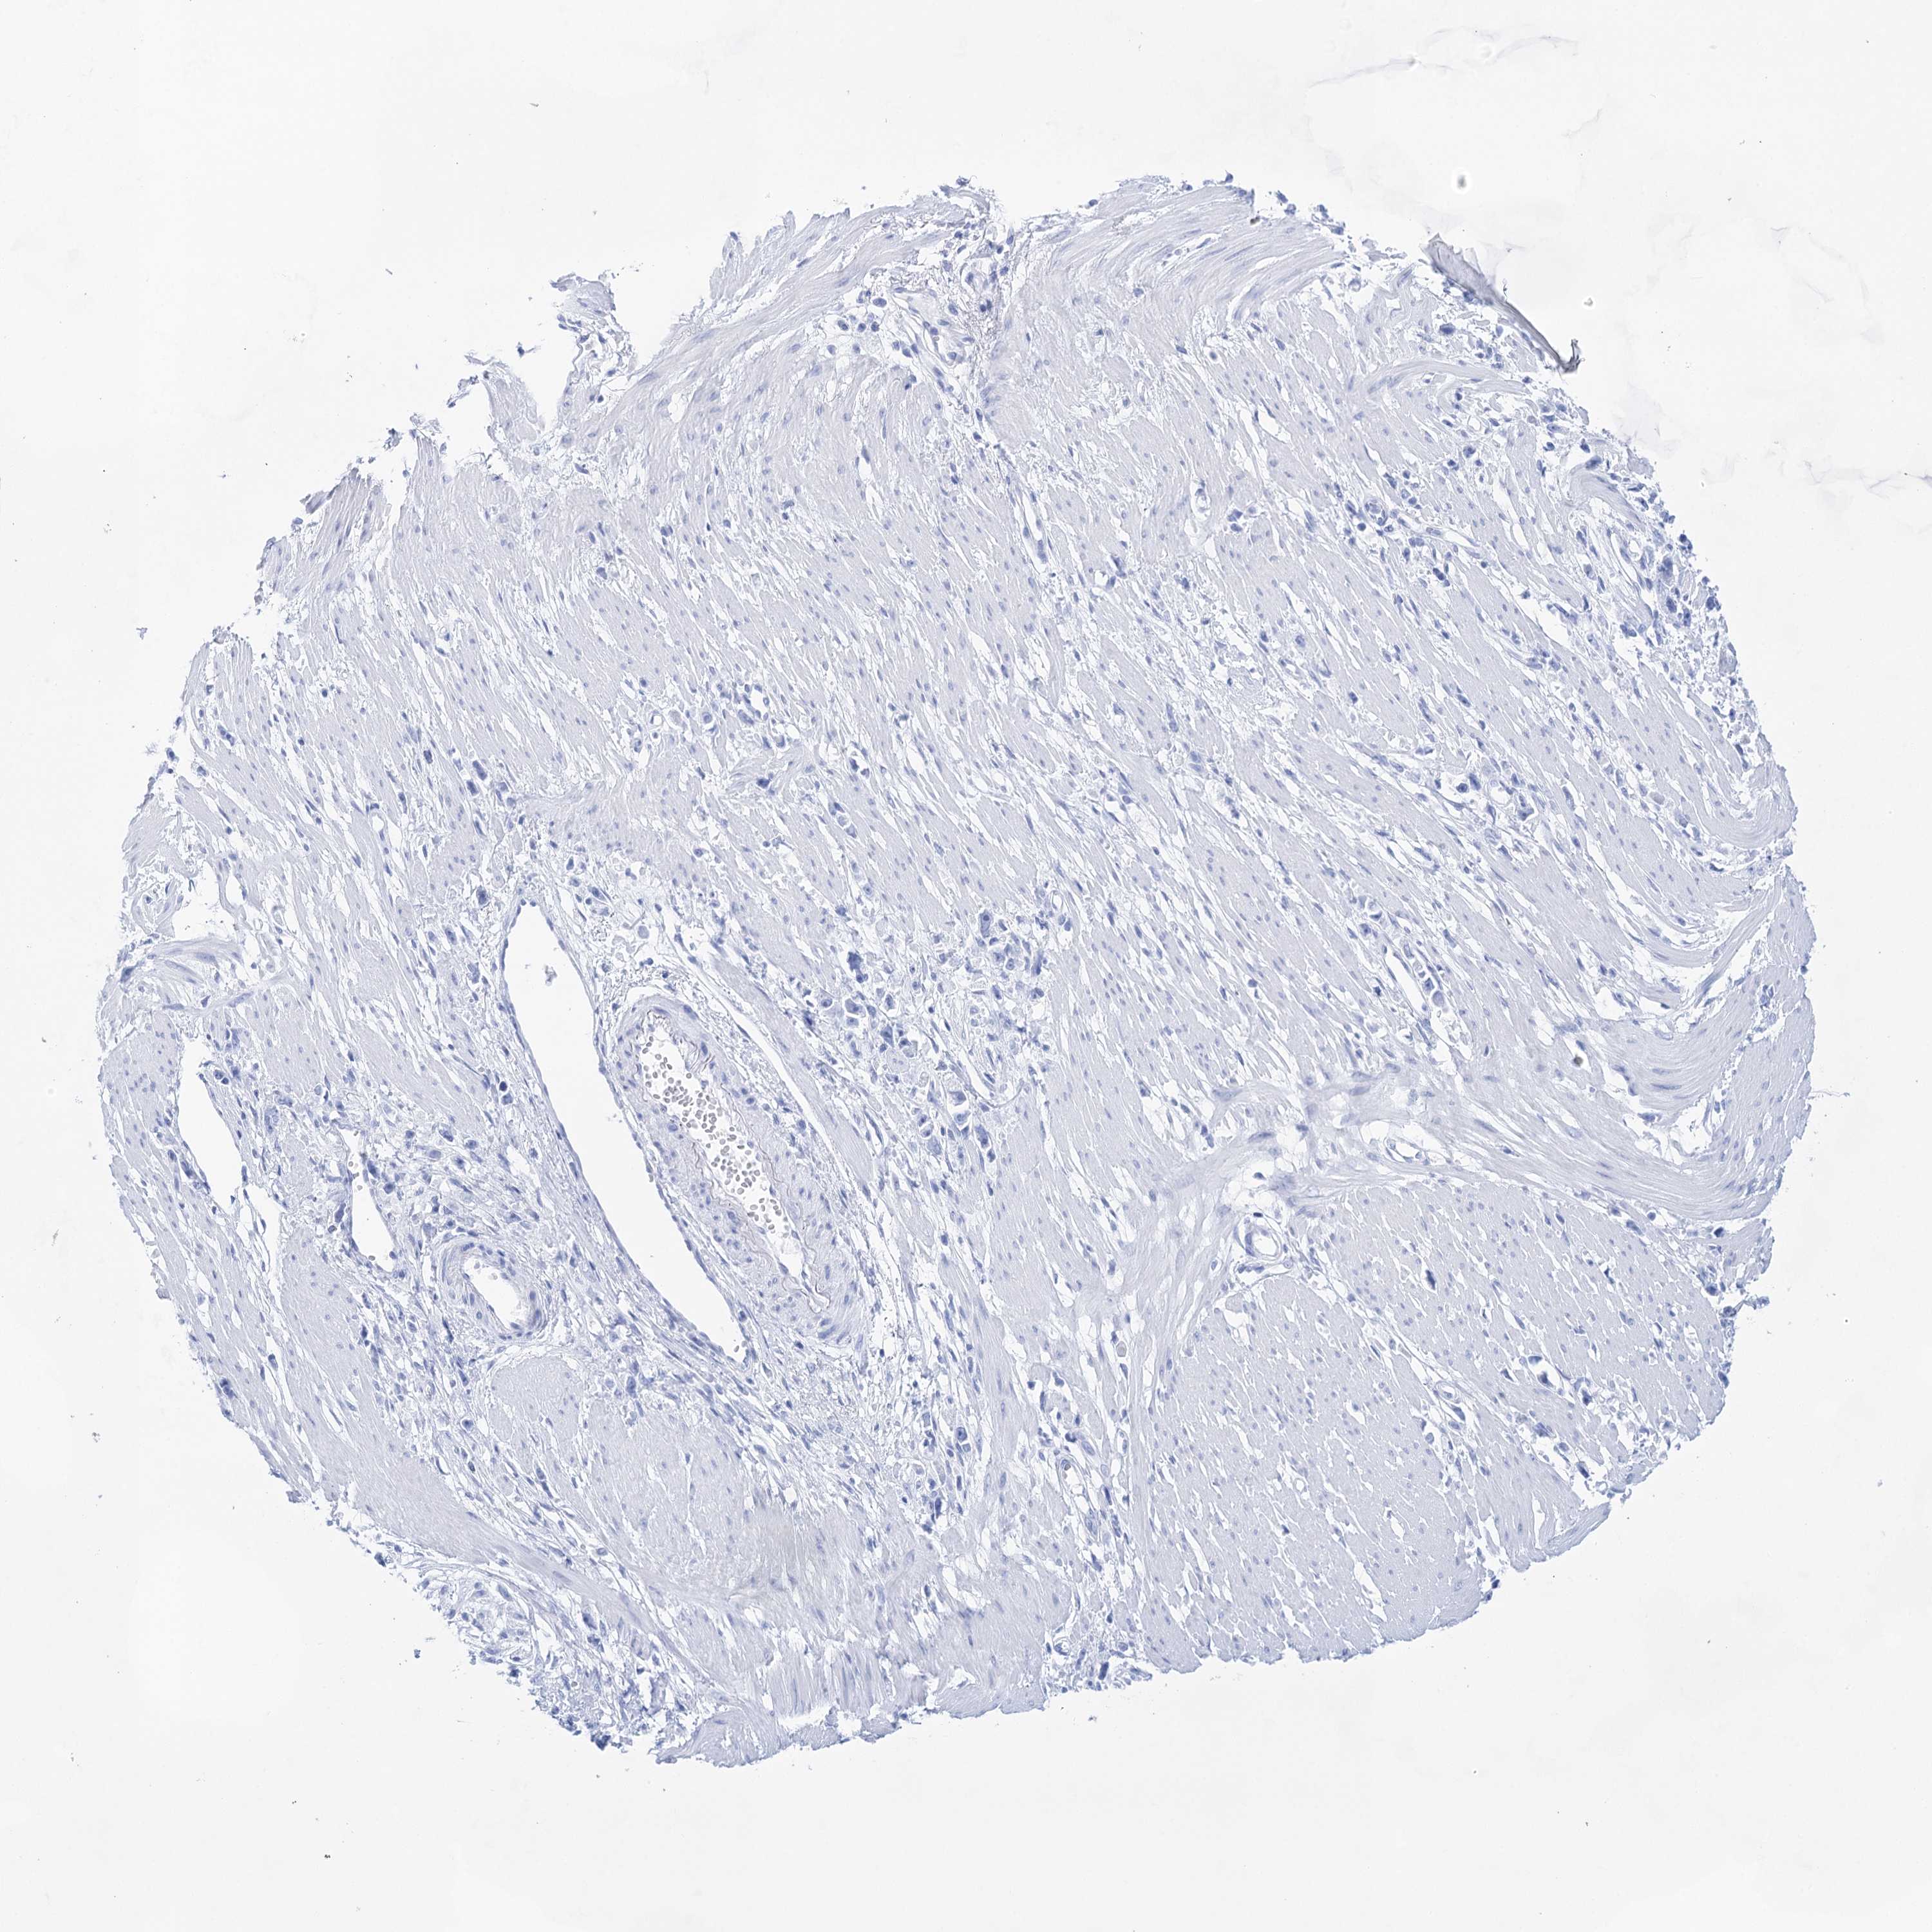

STOMACH CANCER - Protein expressioni

A mouse-over function shows sample information and annotation data. Click on an image to view it in a full screen mode. Samples can be filtered based on level of antibody staining by selecting one or several of the following categories: high, medium, low and not detected. The assay and annotation is described here.

Note that samples used for immunohistochemistry by the Human Protein Atlas do not correspond to samples in the TCGA dataset.

Antibody stainingi

Antibody staining in the annotated cell types in the current human tissue is reported as not detected, low, medium, or high, based on conventional immunohistochemistry profiling in selected tissues. This score is based on the combination of the staining intensity and fraction of stained cells.

Each image is clickable and will lead to virtual microscopy that enables deeper exploration of all samples and also displays staining intensity scores, fraction scores and subcellular localization as well as patient and tissue information for each sample.

Adenocarcinoma, NOS